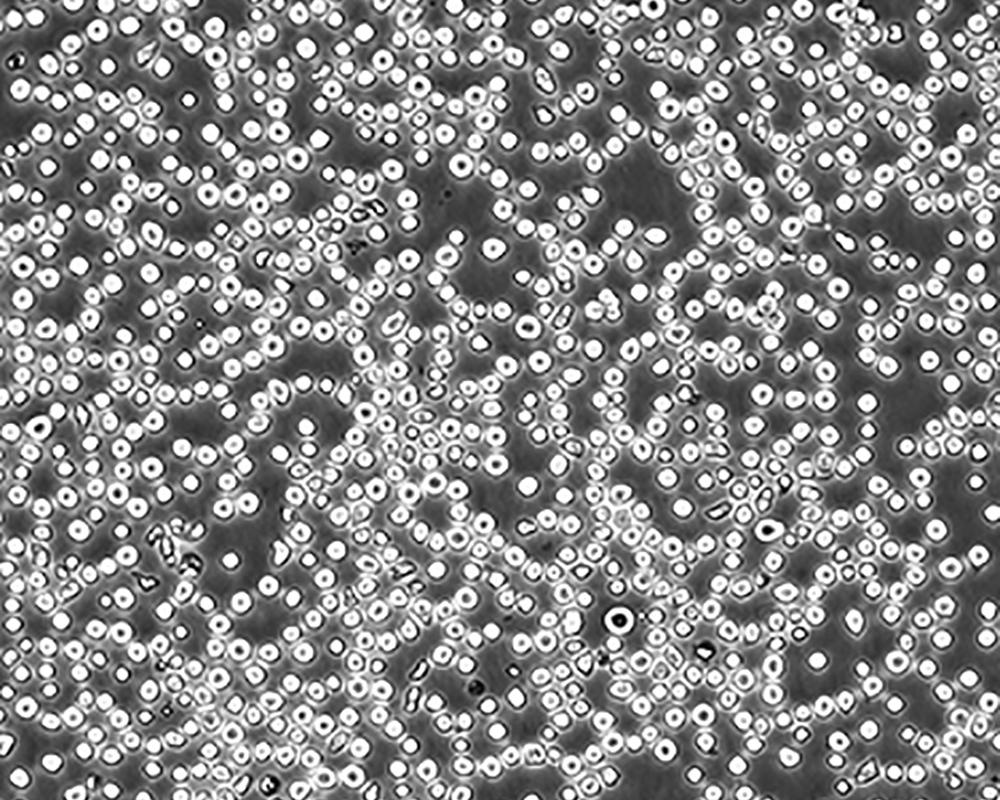

生長特性 suspension

形態特征 lymphoblast

細胞描述 CEM/C1是人T細胞白血病細胞株CCRF-CEM(見ATCC CCL-119)具有喜樹堿抗性的衍生株。1991年細胞株選擇并亞克隆了對CPT的抗性。細胞表現出對CPT類似物水溶性的托泊替康和非水溶性的9-氨基-CPT及10,11-亞甲二氧基-CPT具有交叉抗性。CEM/C1細胞對CPT的敏感性較母系CEM細胞低31倍。CEM/C1細胞表現非典型的多藥抗性和轉換拓補異構酶I催化活性。對CPT的抗性維持6個月以上。

細胞傳代步驟 如果細胞密度達80%-90%,即可進行傳代培養。1. 棄去培養上清,用不含鈣、鎂離子的PBS潤洗細胞1-2次。2. 加2ml消化液(0.25%Trypsin-0.53mM EDTA)于培養瓶中,置于37℃培養箱中消化1-2分鐘,然后在顯微鏡下觀察細胞消化情況,若細胞大部分變圓并脫落,迅速拿回操作臺,輕敲幾下培養瓶后加少量培養基終止消化。3. 按6-8ml/瓶補加培養基,輕輕打勻后吸出,在1000RPM條件下離心4分鐘,棄去上清液,補加1-2mL培養液后吹勻。4. 將細胞懸液按1:2到1:5的比例分到新的含8ml培養基的新皿中或者瓶中